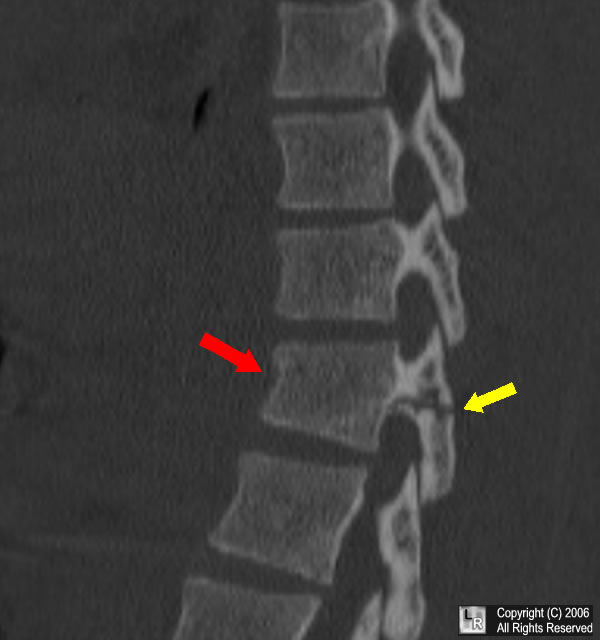

Wedge compression fracture L1 Image

Wedge compression fracture L1 Image Vertebral Wedge Fracture Radiology Spinal wedge (compression) fractures are hyperflexion injuries to the vertebral body resulting from axial loading. The images show a compression fracture. The common radiographic findings associated with vertebral compression fractures include a wedge deformity, linear zone of condensation, a step defect (which represents failure. 5 it is important to determine whether there are. As long as there is no free. Vertebral Wedge Fracture Radiology.